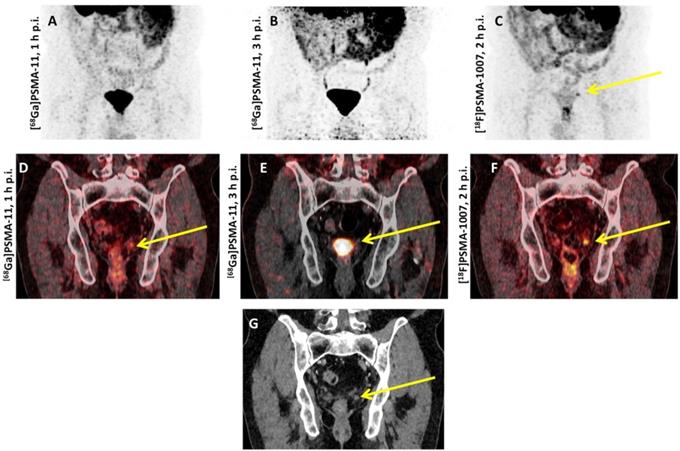

Figure 3

Head-to-head comparison of [68Ga]PSMA-11 vs. [18F]PSMA-1007 PET/CT. Biochemical relapse after prostatectomy, localized in the fossa of the seminal vesicle on the left. (A,D) early and (B,E) late [68Ga]PSMA-11 PET/CT scans which showed an equivocal finding. The residual activity of [68Ga]PSMA-11 3 hours p.i. was too low for a final interpretation (E). The additionally performed [18F]PSMA-1007 revealed the relapse with a PSMA overexpression, demonstrated on the maximal intensity projection (C) and on the coronal tomogram (F). The relapse showed a correlate on the low-dose CT (G).

Spearheaded by Giesel et al., [18F]PSMA-1007 was first tested in a patient with biochemically recurrent PCa and this imaging agent detected micrometastases along the retroperitoneum and iliac arteries [67]. Thereafter, this compound was further evaluated in a Phase 1 trial using three healthy volunteers and ten PCa patients (injection-to-imaging intervals, 1 h and 3 h). First and foremost, the authors reported on no adverse events and the mean effective dose was comparable to other 18F-labeled PSMA PET agents (injected amount of radiotracer activity, 200-250 MBq). The notably reduced renal excretion of [18F]PSMA-1007 may further increase diagnostic accuracy for small lymph node metastases in the pelvis (particularly if located along the ureters) or to assess lesions below/adjacent to the urinary bladder, i.e. local recurrence (clearance via urinary tract for [18F]PSMA-1007 during the first 2 h p.i., 1.2% of the injected activity vs. 11% for 18F-DCFPyL) [14, 31]. Beyond a report on visual assessment, the authors also performed a histopathological comparison of patients who underwent prostatectomy and the diagnostic findings were validated by examinations of harvested tumor tissue [31]. Based on these encouraging findings, Rahbar et al. evaluated 100 patients with biochemical relapse in a retrospective setting and distinctive detection frequencies among patients with different PSA levels were noted, with rates of positive scans as follows: 86%, 89%, 100% and 100% among patients with PSA levels of ≤0.5, 0.51-1.0, 1.1-2.0 and > 2.0 ng/ml, respectively [68]. Giesel et al. provided further insights on the diagnostic efficacy of [18F]PSMA-1007 in >250 patients suffering from biochemical recurrence after radical prostatectomy: Further improvements in the overall detection rate were recorded, in particular in low and ultra-low PSA levels of 0.5-<1 and 0.2-<0.5 ng/mL with detection rates of 74.5% and 61.5%, respectively [69]. Rahbar and coworkers also reported on the superior diagnostic performance of [18F]PSMA-1007 in comparison with [68Ga]PSMA-11, in particular for segregating local recurrence from physiological radiotracer excretion [70]. Similar to [18F]DCFPyL, [18F]PSMA-1007 has an increased lesion detection rate at 120 min p.i. compared to an early imaging protocol 60 min p.i., along with a significant increase in SUVmax [71] (Figure 3). The recently launched “[18F]PSMA-1007 Global Initiative“ aims to establish further phase I/II trials and these results may reveal insights into the added value of this imaging agent among high-risk individuals [72]. Recently, Rauscher et al. reported on a matched-pair comparison in patients undergoing either [68Ga]PSMA-11 or [18F]PSMA-1007 PET/CT. For the latter agent, a higher number of lesions with quantitatively increased radiotracer accumulation attributed to benign lesions were found, which further emphasizes the need of increasing reader's confidence to identify such pitfalls [73]. Thus, incorporation of structured reporting systems may be of relevance for an accurate scan interpretation, in particular when reading an 18F-labeled PSMA PET scan [57].